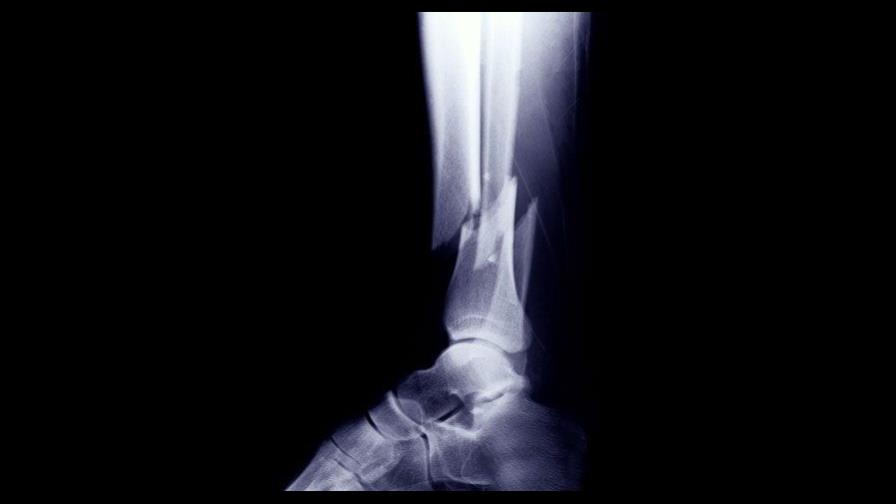

Abiertas: son cuando los extremos del hueso roto salen al exterior, destruyendo la piel y/o los músculos, presentándonos una herida.

Cerradas: son cuando se rompe un hueso sin salir al exterior.

Subtipos de fracturas

Tallo verde: en este caso el hueso no se rompe, pero se deforma (esto ocurre en los infantes)

Por impacto: el hueso se incrusta dentro de sí mismo, acortando su tamaño.

Conminuta: es cuando parte del hueso es destruido por un gran peso que pasa sobre él.

Fisura: cuando el hueso se agrieta, pero no se rompe.